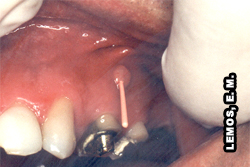

Abscesso Dento-alveolar Crônico (Abscesso Perirradicular Crônico)Consiste em uma lesão inflamatória de origem pulpar que é caracterizada pela presença de uma lesão de longa duração que resultou em um abscesso que está drenando para uma superfície mucosa (fístula) ou cutânea.

*Fístula: Lesão congênita ou adquirida em que se comunicam, por meio de canal por onde transita matéria, duas cavidades orgânicas ou uma cavidade orgânica e o meio exteriorDicionario Aurélio

Etiologia:Resulta da necrose pulpar e geralmente está associada a uma periodontite apical crônica que formou um abscesso. O abscesso caminhou por meio do osso e do tecido mole para formar um trajeto fistuloso com abertura na mucosa oral, ou, algumas vezes, na pele da face.

Também podem drenar através do periodonto pelo sulco periodontal e dessa maneira pode mimetizar um abscesso periodontal ou uma bolsa periodontal.

Sinais e Sintomas:Quando a drenagem ocorre, o abscesso perirradicular crônico é assintomático, exceto quando existe um fechamento do trajeto fistuloso, o que pode causar dor. Os achados clínicos, histopatológicos e radiográficos são semelhantes a sua forma aguda. Uma característica adicional é a fístula.